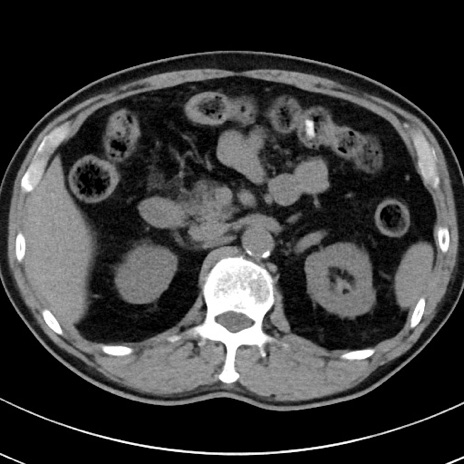

【腹部TIPS】症例29 参考症例 CT(横断像)

症例

70歳代男性